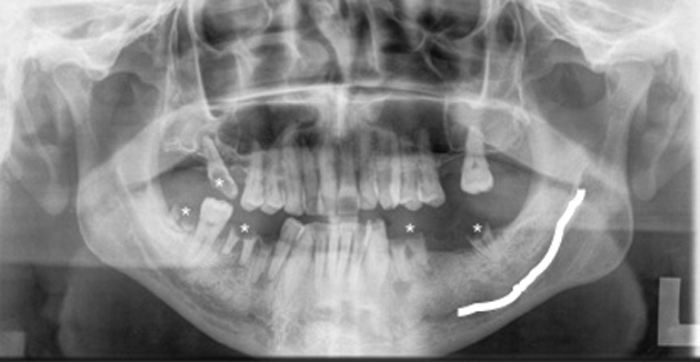

A commonly used radiograph is the orthopantotomogram (OPT). An OPT is a horseshoe shaped tomographic slice of both jaws, which can be useful in the assessment of caries, periodontal and periapical infections (Figure 5). It is a technique which is prone to positional errors and artefacts which can affect reliability of interpretation. Cone beam CT is being increasingly used in the dental profession but its use specifically for caries assessment is not recommended [2].

Figure 5: OPT of a different patient showing multiple carious teeth (*).

The left inferior alveolar nerve (white line) is easily identified.